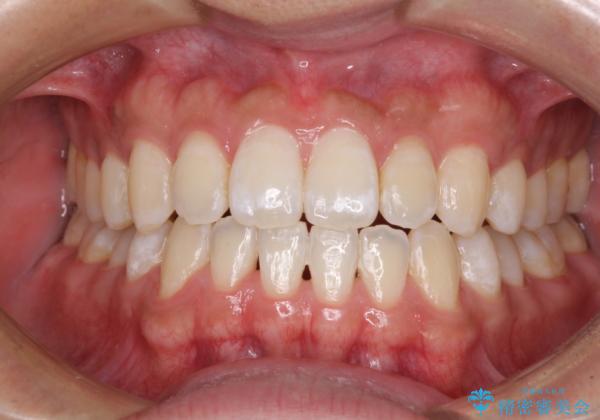

下顎前歯と上顎の部分矯正

- 上下の前歯の叢生を気にして来院された患者様です。

前歯のみの矯正治療を希望でしたが、上顎臼歯が舌側転位していたため、上顎は全体を、下顎は前歯のみを矯正治療することとしました。

矯正治療は上下全顎を行うことが大前提ですが、費用などの点から、今回は部分矯正を選択することとなりました。

患者様本人は咬みにくさを感じていないようですが、部分矯正は咬み合わせの改善が困難であることが多く、咬みにくさが残ることがあります。